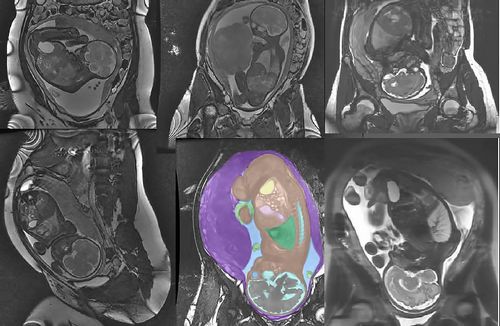

- УЗД і доплерографія з метою виявлень патологій матково-плацентарного і плодо-плацентарного кровотоку.

- Високоточна комп'ютерна томографія (оцінка стану малюка за т.зв. шкалою Фішера).